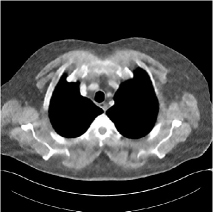

Fig. 3: Three examples (from top to bottom) of the reconstructed testing images using Momentum-Net with SimpleCNN (the second column), with SimpleCNN-RSN (the third column), and with Dn-RSN (the fourth column). The compared WavResNet denoised images are shown in the first column, and the reference images are in the fifth column. See their FBP images in Fig. 4.

Refer to caption

Fig. 4: FBP images of test examples.

Fig. 2 shows that the proposed Momentum-Net with SimpleCNN decreases RMSE dramatically in the first 30 layers, and tends to converge in 50 layers. The Momentum-Net reduces the mean RMSE value by 4.5 HU and gives smaller standard deviations in RMSE, compared to WavResNet, as reported in Table 1. This implies that the proposed Momentum-Net with SimpleCNN can improve both the accuracy and stability of low-dose CT image reconstruction than a state-of-the-art image denoising deep NN, WavResNet. The proposed Momentum-Net with SimpleCNN better removes noise and streak artifacts than WavResNet. It also provides clearer reconstructions of some details; see, in Fig. 3, the boundaries shown in the zoomed region at the top-right corner in the first example, the arrow pointed structures in zoomed areas of the second example, and the arrow pointed tissues in the left zoomed region in the third example.

3.3 Momentum-Nets involving RSN-based training

We show the reconstructed examples by Momentum-Net with SimpleCNN-RSN and Dn-RSN in the third and fourth columns of Fig. 3 respectively. Comparing the first three and the last columns in Fig. 3, we observe that Momentum-Net with SimpleCNN-RSN provides generally noisier reconstructions than WavResNet and Momentum-Net with SimpleCNN. However, Momentum-Net with SimpleCNN-RSN sometimes can provide clearer details than WavResNet. For example, in the right zoomed box of the second example, Momentum-Net with SimpleCNN-RSN shows better reconstruction quality for the arrow pointed structures than WavResNet, and in the left zoomed box in the third row, the former gives clearer small tissues marked by red arrows than the latter. Table 1 reports that Momentum-Net with SimpleCNN-RSN is approximately 2.9 RMSE (HU) higher than WavResNet, while it has smaller standard deviations. This implies that Momentum-Net with SimpleCNN-RSN is more stable than WavResNet, although it may not provide better image qualities. Momentum-Net with Dn-RSN, however, provides the worst visual and numerical results among the compared four methods in this paper.